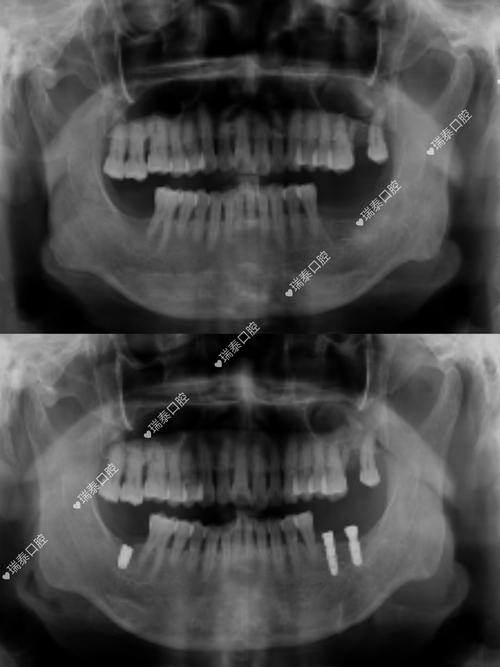

- 提供详细信息(如果可能): 如果你知道自己种植牙的品牌、型号或牙冠的具体材料类型,最好能提供给医生或技师,这有助于他们评估潜在影响并选择合适的成像方案。

- 咨询你的牙医: 如果你即将进行MRI检查,不确定自己的牙冠材料,或者对检查有顾虑,可以提前咨询你的种植牙医生。